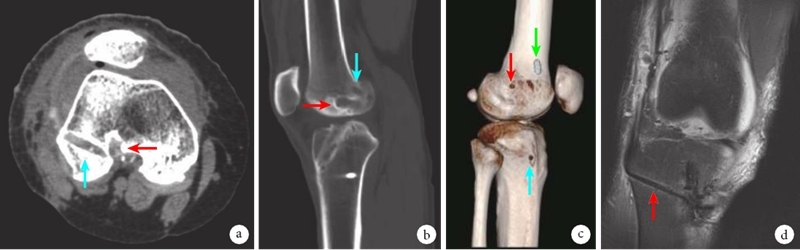

图3 骨隧道位置示意图 a、b.右膝关节轴位及矢状位CT示新制备股骨隧道(蓝色箭头)及原股骨隧道(红色箭头);c.CT三维重建示后外侧束骨隧道在股骨外侧皮质出口(红色箭头)、ALL骨隧道在胫骨外侧皮质出口(蓝色箭头)、前内侧束在股骨外侧经Endo-Button悬吊固定位置(绿色箭头);d.右膝关节MRI示ALL骨隧道(红色箭头)